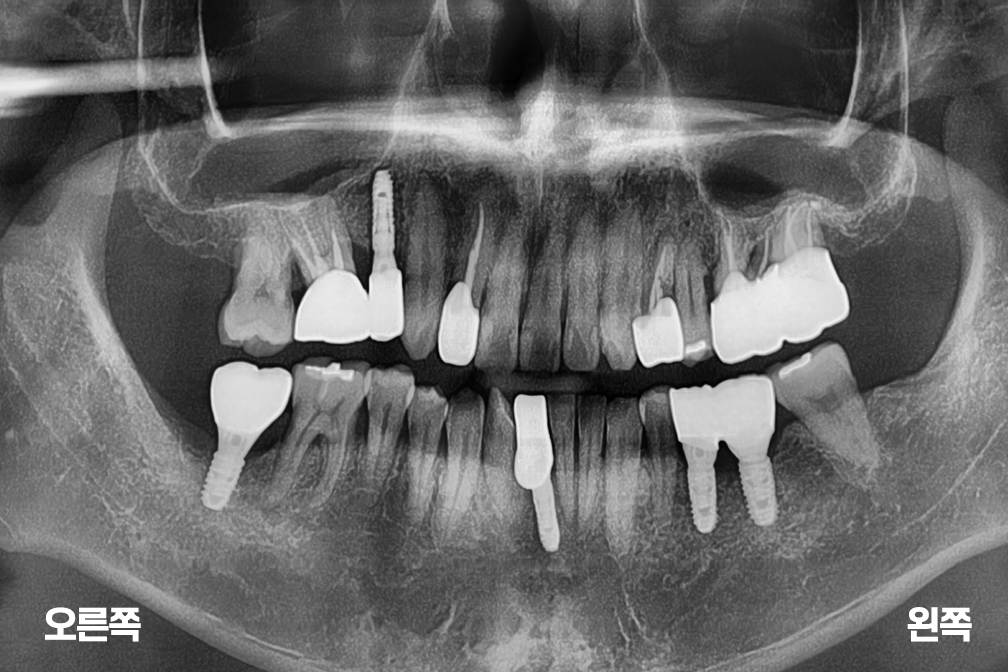

임플란트 오른쪽 위 앞니 임플란트 + 아래 양쪽 임플란트 수술

Before 2025년 8월 16일

After 2026년 3월 23일-